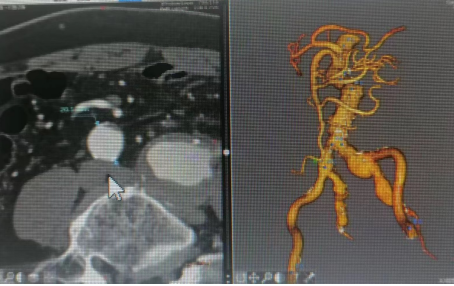

术前血管造影

但新的困难出现在诊疗团队面前:患者的瘤体解剖条件复杂,有瘤颈短且扭曲、入路扭曲等情况,微创手术容易发生隔绝不彻底、术后内漏等情况。这些困难无疑是对科室团队技术极大的考验,科室联合医院麻醉科、心内科、介入手术室等兄弟科室,在术前为患者制定了周密的手术方案。在各专科密切配合下,为患者施行了“双侧股动脉穿刺+经皮超选择性动脉造影+经皮选择性动脉置管栓塞术+腹主动脉瘤腔内隔绝术+髂动脉瘤腔内隔绝术”,成功为老人摘除血管肿瘤,拆除体内“炸弹”。